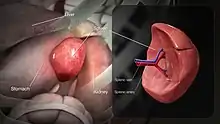

In humans, the spleen is purple in color and is in the left upper quadrant of the abdomen.[3][9] The surgical process to remove the spleen is known as a splenectomy.

Spleen Laparoscopic view of human spleen

Laparoscopic view of human spleen